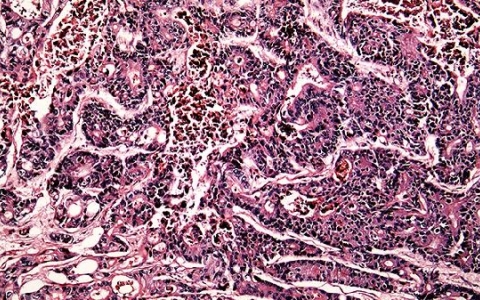

伴嗜酸粒细胞升高的基因

嗜酸粒细胞是人体免疫系统中的一种重要白细胞,在免疫反应和过敏反应中扮演着关键角色。嗜酸粒细胞升高可能与多种基因相关,这些基因在不同疾病情境下可能表现出不同的特征